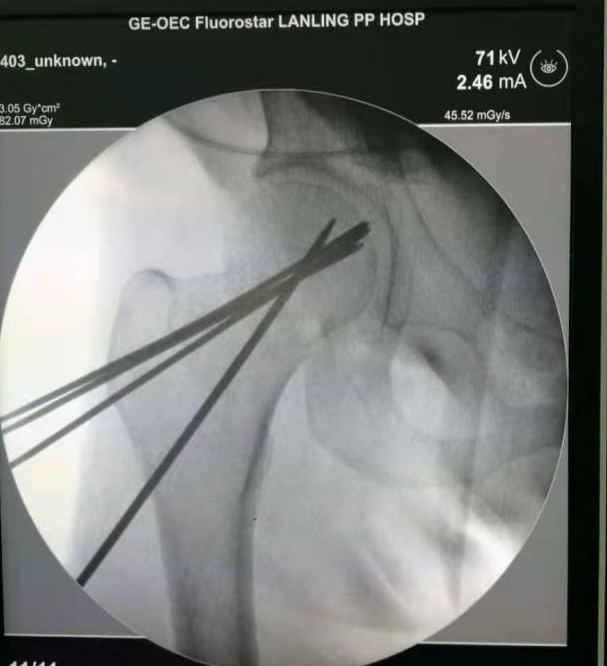

术前麻醉后给予骨折牵引复位成功,通过克氏针穿刺精确定位,将防旋交叉钉系统准确植入。

图3 精确定位并置入防旋交叉钉系统